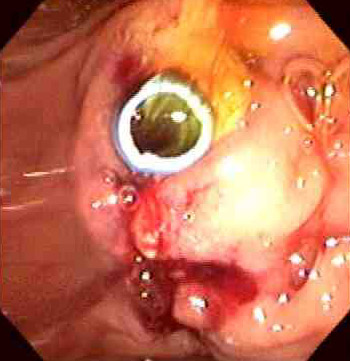

| This adenocarcinoma arose in the ampulla of Vater. Primary small intestinal carcinomas are very rare, but the majority of those that do occur arise in the region of the ampulla, where they may become symptomatic through biliary or pancreatic duct obstruction. The appearance of such a mass on esophagogastroduodenoscopy is seen below, and following placement of a stent for drainage. |